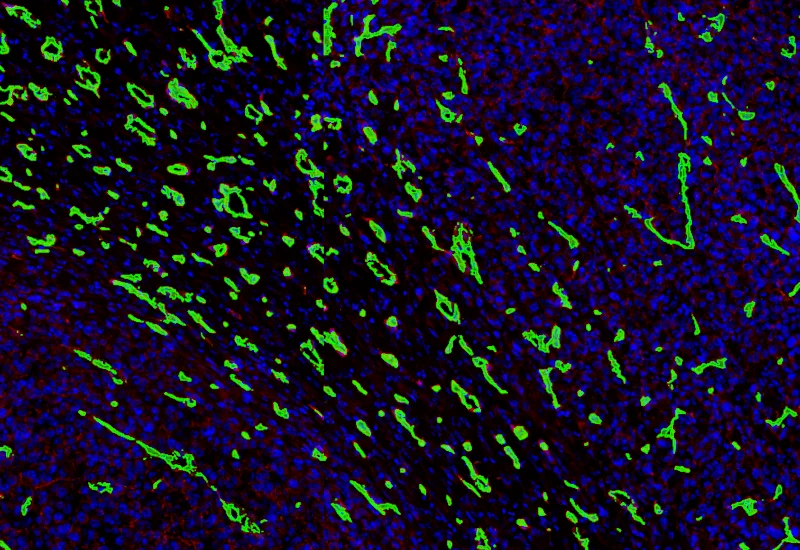

Tumor detection

Vessel detection